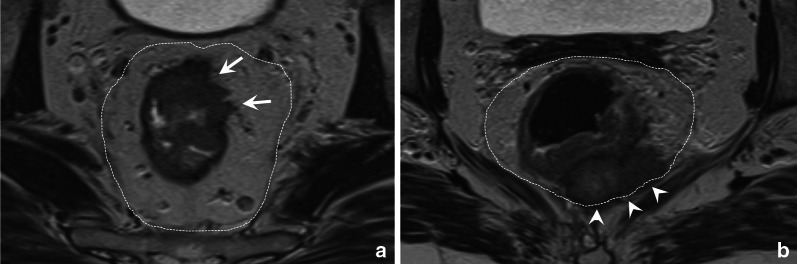

Fig. 1.

Axial T2-weighted images of a low risk T3ab tumour without MRF involvement (a) and a high-risk T3cd tumour with MRF involvement (b). The left patient is a 52 year old male patient with a tumour that extends beyond the muscularis propria from approximately 12 till 2 o’clock (white arrows) with an extramural invasion depth of < 5 mm. There is a sufficient margin (> 1 mm) between the tumour and MRF. The right patient is a 55-year-old female patient with extensive extramural invasion from 4 to 6 o’clock with broad-based involvement of the MRF (white arrowheads)